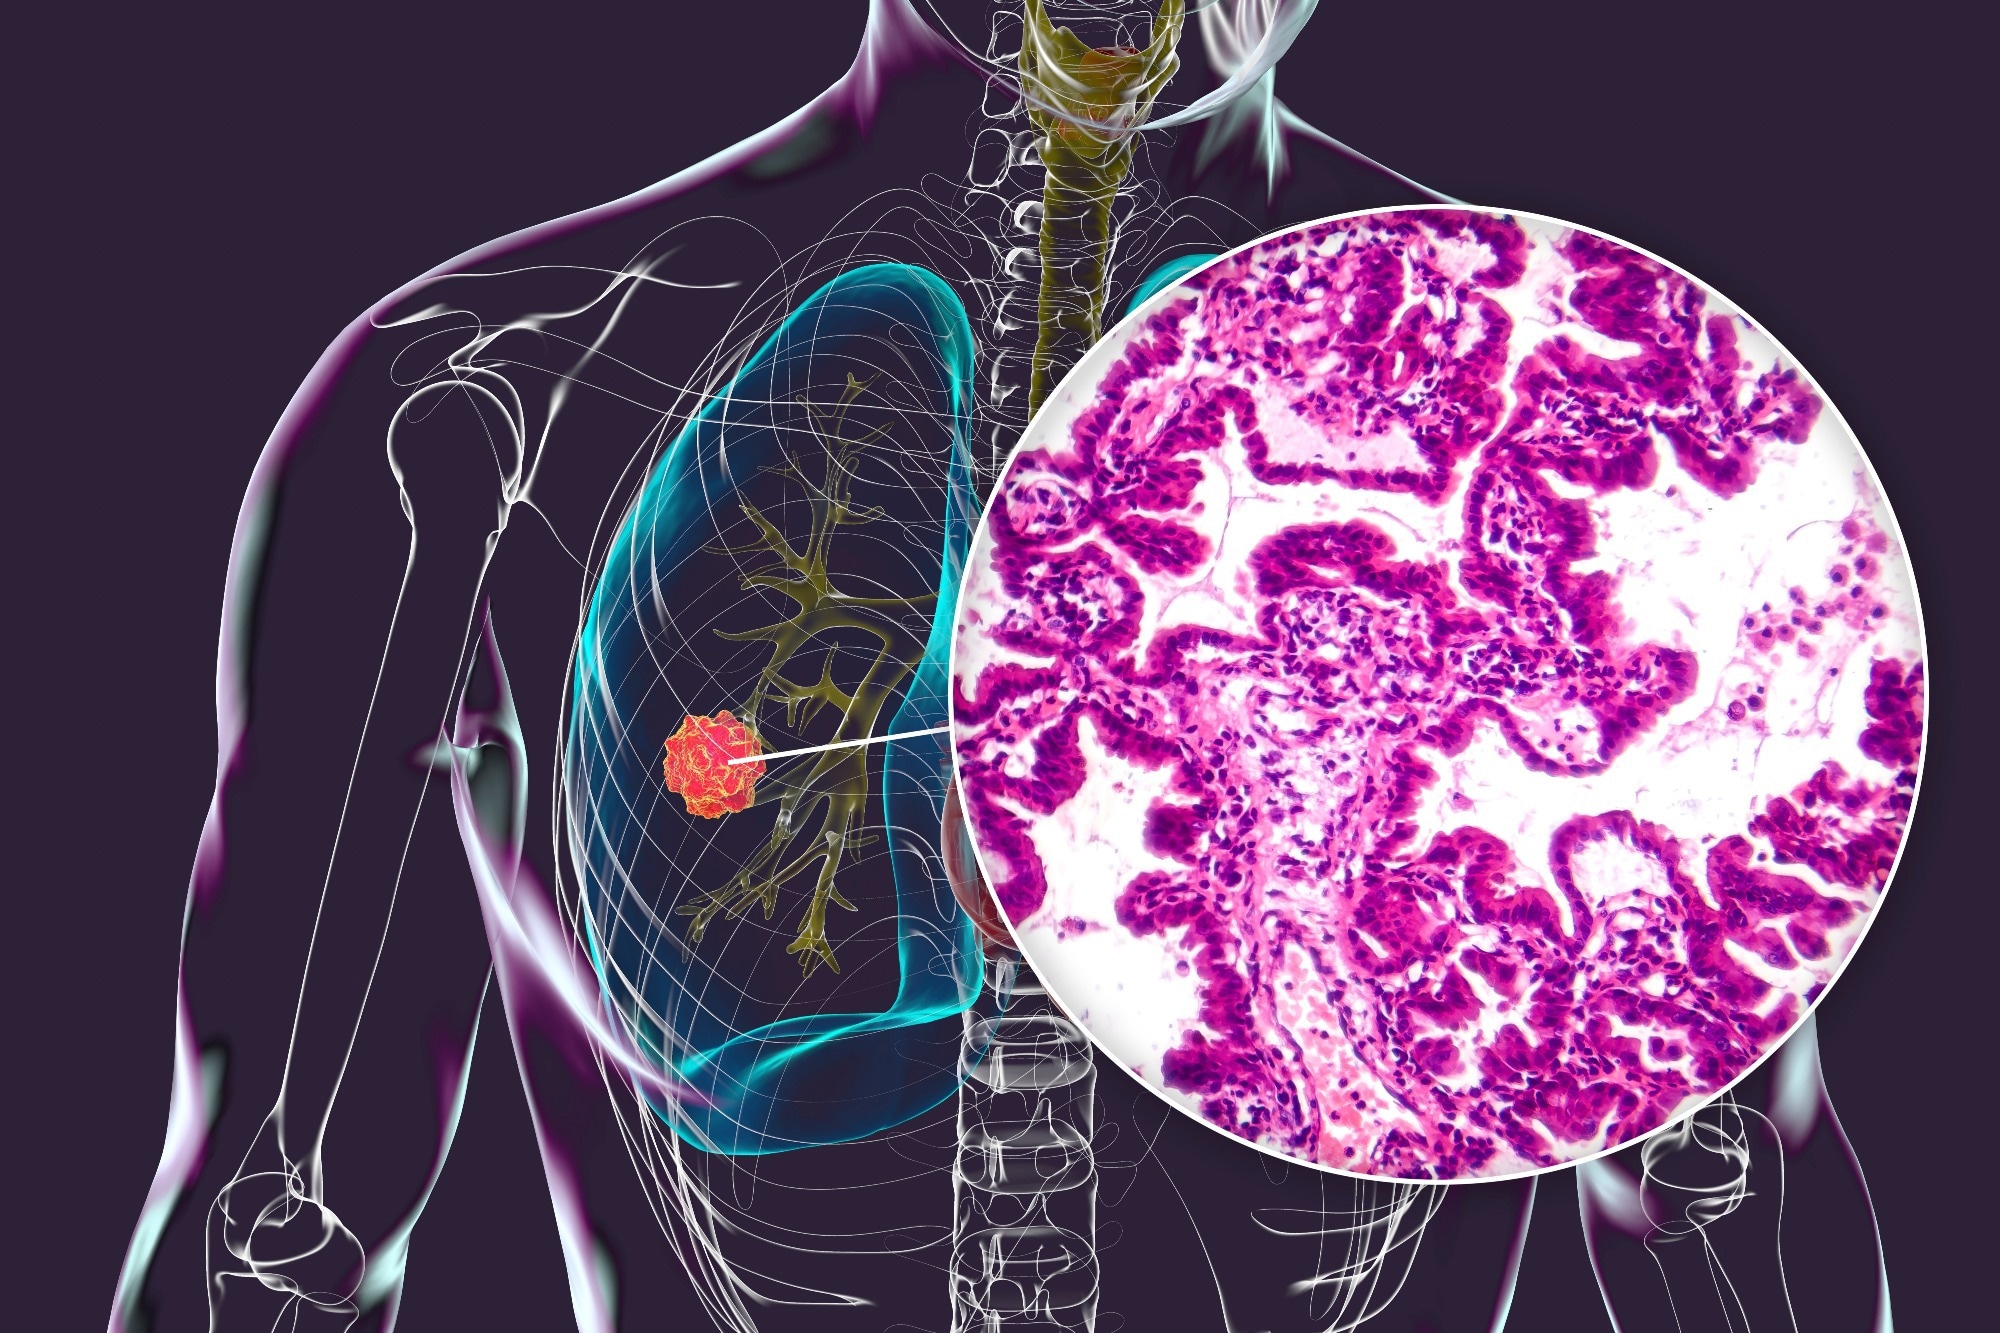

A human body with transparent skin showcasing lung cancer, 3D illustration complemented by a light micrograph of the lung adenocarcinomaStudy: Real-world deployment of a fine-tuned pathology foundation model for lung cancer biomarker detection. Image credit: Kateryna Kon/Shutterstock.com